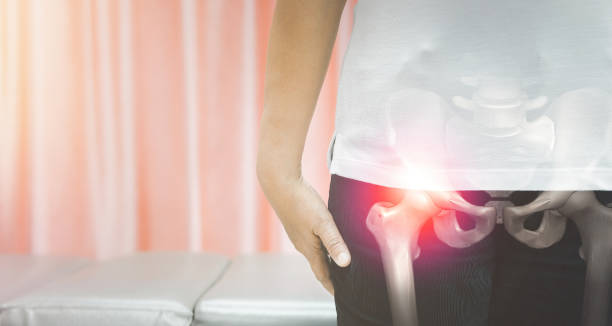

고관절 수술후 회복기간- 수술 후 1주일: 치료와 통증 관리

수술 후 1주일은 가장 중요한 시기입니다. 이 때에는 처음 수술에 대한 통증이 가장 심하며, 치료와 통증 관리에 집중해야 합니다. 수술 부위를 올바르게 관리하고, 의사의 지시에 따라 정확히 약물을 복용하는 것이 중요합니다. 또한, 특별한 동작을 하지 않도록 주의해야 합니다. 1주일 동안은 휠체어를 사용하거나 보조기를 사용하는 것이 좋습니다.